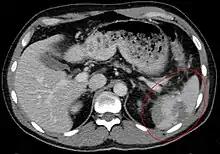

Un scanner de l'abdomen peut donner un aperçu plus complet des blessures spléniques et autres, pouvant montrer une fracture, des lacérations ou un hématome sous-capsulaire. La gravité des lésions peut être ainsi classée[9] ce qui permet une optimisation de la prise en charge et une diminution sensible de la nécessité d'une prise en charge chirurgicale[10].